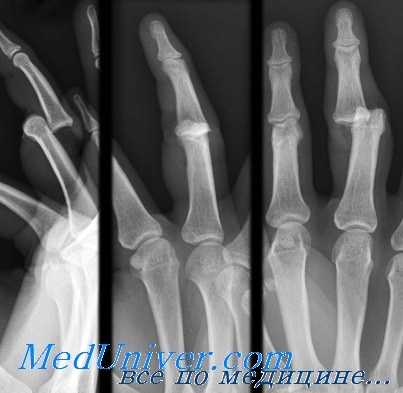

а-в - различные виды вывихов в пястнофаланговом суставе большого пальца:

а) простой неполный вывих,

б) простой полный вывих,

в) полный вывих

г-д - вывих большого пальца правой кисти в пястнофаланговом суставе у пожилого больного наступил много лет тому назад. Вправление вывиха оказалось безуспешным, функция большого пальца была нарушена (а). Нарушение функции пальца усугублялось деформирующим артрозом, возникшим у больного за эти годы.

На рентгеновском снимке видно (б), что основная фаланга большого пальца вывихнулась к ладони.

В первом запястно-пястном суставе обнаруживается тяжелая, а в остальных суставах умеренная форма деформирующего артроза